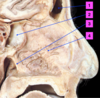

Identify 1

Superior Concha

Identify 2

Medial Concha

Identify 3

Inferior Concha

Identify 1

Frontal Sinus

Identify 2

Sphenoidal Sinus

Identify 3

Choanae

Identify 4

Nasal Septum

Identify1

Pharyngeal Tonsils

Identify2

Auditory Canal

Identify3

Laryngeal Inlet

Identify4

Pharyngo-Oesophageal Junction

Identify 5

Oesophagus